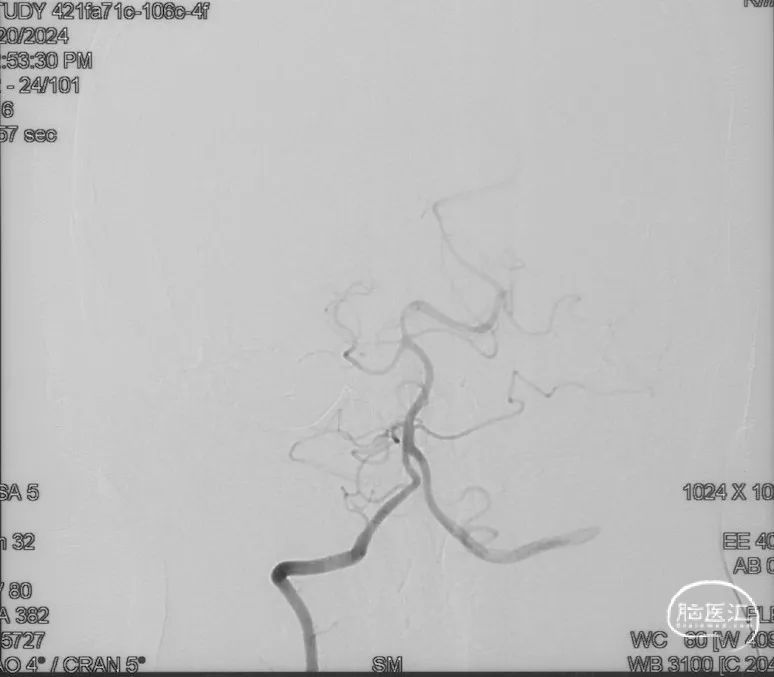

影像学的随访

术后9m

右侧颈内动脉造影未见瘘口显影及静脉早显

右侧颈外动脉造影未见瘘口显影及静脉早显

左侧椎动脉造影未见瘘口显影及静脉早显